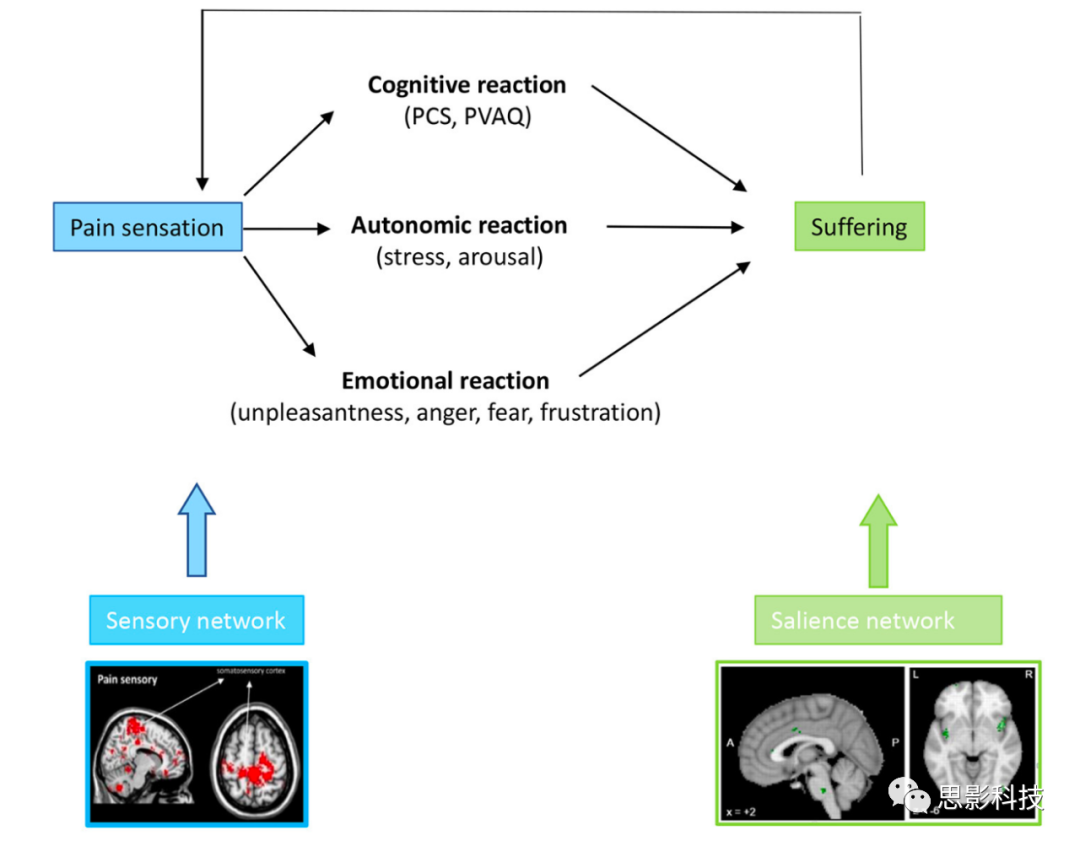

疼痛刺激通常会导致负面的认知、情感和自主反应,表现为由中央通路处理的与疼痛相关的痛苦。这在解剖学上与编码疼痛刺激的行为相关性和中央交感控制网络的突显网络重叠。当疼痛持续的时间超过愈合时间并变成慢性时,与疼痛相关的体感皮层活动可能会与自我表征的默认模式网络功能性地连接,即,它成为自我感知的固有部分。这很可能是为了节省能量而进行的进化适应,通过将疼痛与消耗交感能量的行动分开。通过与前额顶叶中央执行网络的相互作用,这最终可能导致功能障碍。

因此,从解剖学和症状学角度来看,慢性病理性疼痛可以分解为三个可分离但相互作用的通路,包括一个侧向的“疼痛感”通路,一个中央的“痛苦”通路,以及一个下行的疼痛抑制通路(25, 27, 28)(图2,图3)。尽管侧向体感和中央突显通路可以解释疼痛的疼痛感和情感成分,但尚未提出与慢性疼痛中遇到的慢性化和功能障碍相关的因素。我们建议将当前的疼痛网络扩展到三重网络模型以填补这一空白。

当个体报告说他们“疼痛”时,实际上涉及到三个组成部分,即他们有一定量的疼痛感,伴随着特定量的痛苦,持续特定的时间。这三个不同的统一疼痛感知组成部分可以与三个不同的疼痛处理通路相联系(图2)。

图5:慢性疼痛刺激导致认知、情感和自主反应,这在现象学上表现为灾难化、对疼痛的关注、不愉快感、对疼痛的恐惧、愤怒或挫败感以及唤醒/痛苦。这些认知、情感和自主症状都是中央通路中改变活动的现象学表达。(编者注:"灾难化"(Pain catastrophizing)在这里是一个心理学术语,用于描述一种倾向于对疼痛或不适的体验进行过度负面解读的心理状态。这通常包括三个主要方面:放大(Magnification,即过度夸大疼痛的威胁性)、无助感(Helplessness,即在疼痛面前感到无助)和反刍(Rumination,即无法停止关于疼痛的思考)。

总之,疼痛由两个方面组成:由侧向途径编码的感觉疼痛方面,以及由中向系统编码的痛苦方面。痛苦有三个组成部分:认知、情感和自主成分,所有这些都由中向途径处理。因为中向和侧向途径是不同的,人们可以在没有痛苦的情况下体验到疼痛(感觉的完整性),也可以在没有疼痛(感觉的完整性)的情况下体验到痛苦。

疼痛、痛苦和突显网络

图 7:侧向感觉运动通路中疼痛刺激的存在,可以导致由中央突显通路编码的认知、情感和自主反应,表现为痛苦。当疼痛和痛苦变得慢性时,它们会变得具体化,即成为自我的一部分,通过感觉运动皮层与默认模式网络的连接来实现。具体化的疼痛和痛苦随后可能导致身体和认知障碍,可能是通过与运动和中央执行网络的功能失调连接分别进行的。